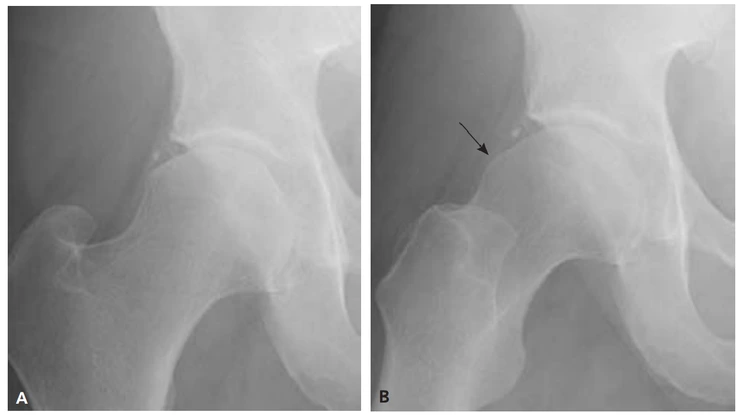

대퇴-비구 충돌중후군은 대퇴와 비구사이의 충돌입니다. Cam 충돌은 대퇴골두의 문제로 발생하는 충돌증후군입니다. 대퇴골두가 비정상적으로 직경이 커지거나, 뾰족한 부분이 생기는 경우에 발생합니다. 특히 고관절을 앞으로 굽힐 때 (고관절 굴곡시) 많이 발생합니다. 커진 대퇴골두나 대퇴 근위부의 융기는(Prominence) 비구순(Labrum)을 손상하게 됩니다. 위의 사진에 우측 X-ray를 보면 대퇴골두가 경부와 만나는 곳에서 융기되어 있습니다. 이 부분이 고관절의 움직임(특히 굴곡)에 의해 지속적인 자극을 주면 비구순(Labrum)이 찢길 수도 있고, 관골구 개연(Rim of Acetabulum)이 손상되기도 합니다. 심지어 관골구(Acetabulum)의 골연골을 박리하기도 합니다.

X-ray상에서는 대퇴골두나 대퇴골근위부에서 튀어나온 융기부분을 확인할 수 있습니다. 그러나 대퇴골두부분의 경우 단순 AP view에서는 정확하게 융기부가 보이지 않는 경우가 많습니다. 이럴 때에는 20도 정도 외전방향에서 촬영을 해야 대퇴골두부분을 더 정확히 확인할 수 있습니다. 이런 촬영방식을 불러 Modified Dunn view라고 합니다. A의 경우 대퇴골두에서 경부로 이어지는 부분이 움푹 들어가 정상적인 모습을 보이지만, 약간만 방향을 틀어 B의 영상(Modified Dunn view)을 얻으면 융기된 부분을 찾아낼 수 있습니다.